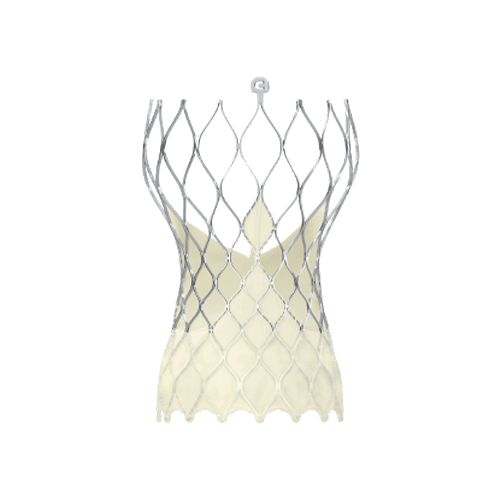

在冠脉保护后,TAVR植入流程顺利开展,选用通过性能优异的递送系统,利用内联鞘兼容患者细小钙化血管,在无snare辅助条件下便可顺利通过小弓和横位心结构,结合Evolut PRO独有的缝合缘对齐技术,在植入过程中控制瓣膜方向最大限度避免冠脉阻挡。